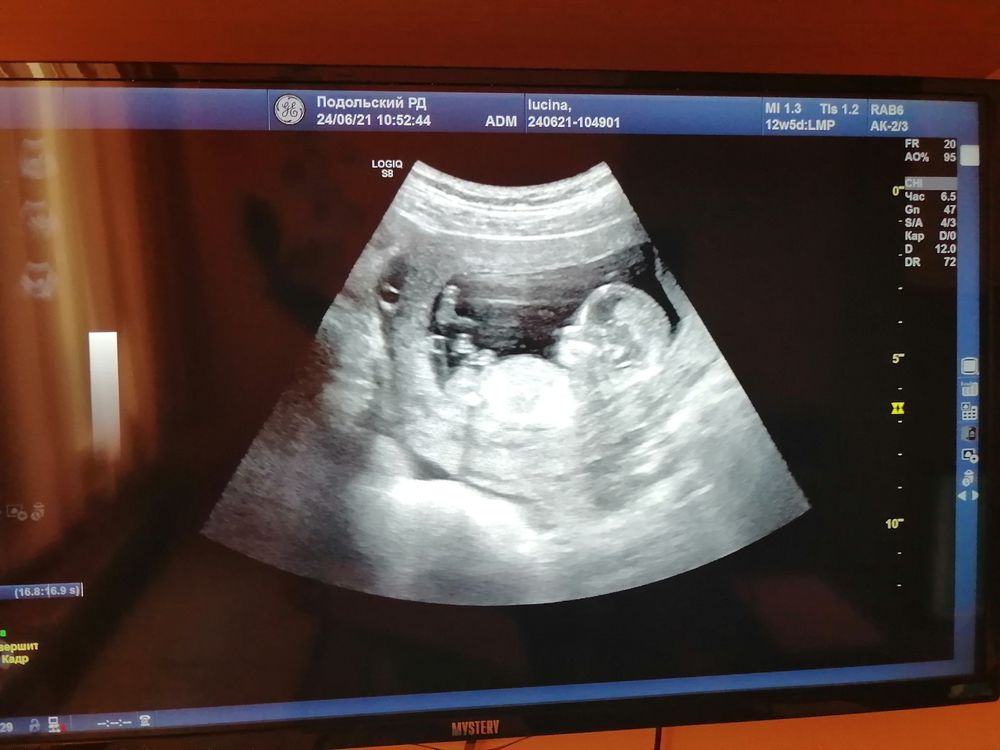

Если бугорок, то на что думаю, то девочка. Наша мадам явно засветила, и в принципе аппарат очень чёткий Изображение

Вот у меня мальчик на 12 неделе. Белый - бугорок половой Изображение

Не знаю, не вижу бугорок, если честно. Ногу вижу вот)) Профиль милый😊

Анастасия, если это бугорок,то это парень)коротенькая пипка вверху у пацанов))

Леночка Лучкина, идёт как палочка если видите и она горизонтально и обычно так у девочек ,но могу ошибаться

Изображение Леночка Лучкина, Это моё УЗИ и вот там этот бугорок который идёт горизонтально к позвоночнику,когда мальчик у него он поднят на 30 градусов говорят

Мама двух мальчишек, а можете мне показать где тот самый бугорок? А то я не шарю, с первыми двумя сразу говорили, что девочки, а тут уже 25 недель и не показывается, решила так узнать, но ничего не поняла